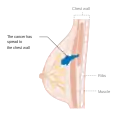

Metastatic or stage 4 breast cancer

Stage 4 breast cancer